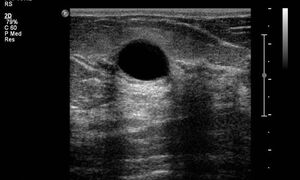

단순낭종

- 무에코

- 균질함

- 둥글거나 타원형

- 주위와 구분되는 명확한 경계

- 후방음영증가

- 누를때 형태가 변하고, 통증이 없다.

- 도플러검사에서 혈관 없슴